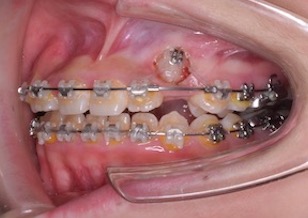

③マルチブラケット装置を装着し、上顎歯列のレベリング(整列)と上顎の左右側犬歯の萌出スペース不足の解消治療を行いました。

④口腔外科にて埋伏歯部の歯肉開窓(切開)を行っていただき埋伏していた左側上顎犬歯にブラケットを装着し正常な位置への移動を行いました。

その後、マルチブラケット装置による個々の永久歯の3次元的な移動を行い、歯列の整直と咬み合わせの確立を行いました。

After Ⅳのお写真は、埋伏していた上顎左側犬歯を牽引途中のお写真です。